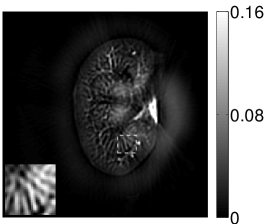

Figure 2(a) shows the image reconstructed by use of the conventional iterative method that utilized a system matrix based on EIR-2. Different values of the regularization parameter from the interval were considered. The reconstructed image with the value of that minimized the RMSE was chosen to represent the best performance of the conventional iterative method. Figure 2(a) and the profile in Figure 2(c) demonstrate that the use of an inaccurate EIR can result in strong artifacts and distortions in images reconstructed by use of the conventional methods.

When the VP algorithm was applied, different values of the regularization parameter from the interval and from the interval were considered. The image that minimized the RMSE was chosen and displayed in Figure 2(b). As revealed by this image and the profiles in 2(c), the VP algorithm yielded an image with fewer artifacts and distortions, and image fidelity was improved as reflected by the reduced RMSE.

The images and EIRs reconstructed by use of the VP algorithm that was based on the 2D imaging model that neglected the SIR are shown in Figures 15 and 16. The latter figure contains results corresponding to different values for the regularization parameter . From Fig. 15, it can be observed that use of the conventional iterative method that utilized the measured EIR resulted in distortions and loss of details in the reconstructed images. Use of the VP algorithm improved the contrast and the details in the reconstructed images (Fig. 15(c) and 16(a)). Furthermore, the images reconstructed by use of the VP algorithm had a more uniform background.

In Figure 17, the results corresponding to use of the 3D imaging model that incorporated SIR effects are shown. The EIR estimated by the VP algorithm is also shown. In Figure 18, images and EIRs reconstructed by use of the VP algorithm with different regularization parameters values are shown.

Similar to the case described above where the transducer SIR was neglected, these results reveal that use of the VP algorithm can produce images with a cleaner background and enhanced spatial resolution than yielded by use of a conventional iterative algorithm that employed the measured EIR. For example, detailed information regarding the vessels near the organ’s periphery was better preserved by the VP algorithm than by the conventional iterative algorithm. These images corroborate our assertion that the VP algorithm can significantly reduce the artifacts and distortions in the reconstructed image. It is also worth pointing out that, unlike the numerical phantom studies, the artifacts and distortions in the images may be caused not only by the inaccurate EIR but also by other factors, such as neglecting acoustic heterogeneities and the variation of the EIRs among the elements of the transducer array. In such cases, the EIR estimated by the VP algorithm represents an effective system impulse response that minimizes the inconsistency between the measured data and the imaging model.